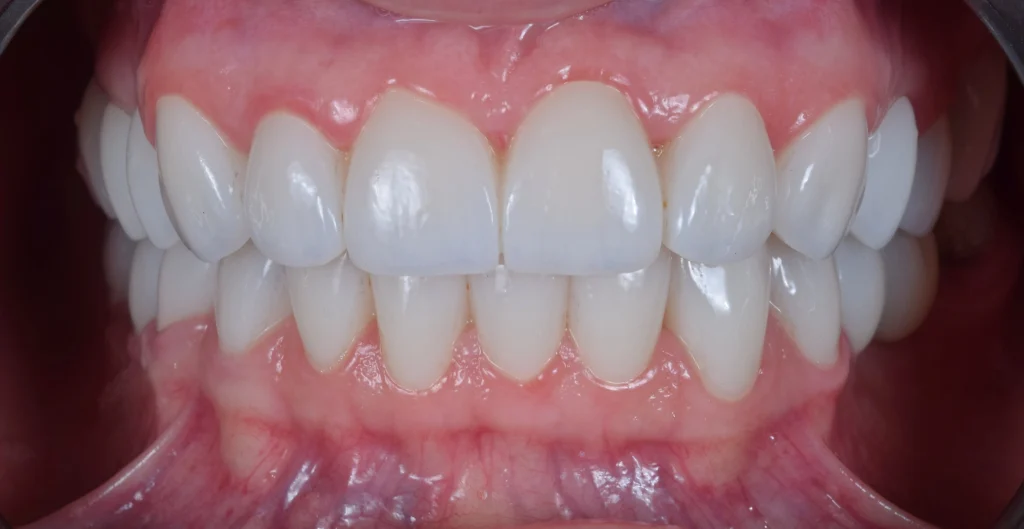

After a short additional healing period of 2 weeks, we delivered the final restorations—high-quality zirconia crowns and bridges. The result is a natural-looking, durable, and radiant smile that perfectly complements her facial features.

Today, she feels more confident than ever before. She can smile, speak, and eat freely again—and most importantly, she is proud to show her new, healthy, and beautiful Hollywood smile.Â